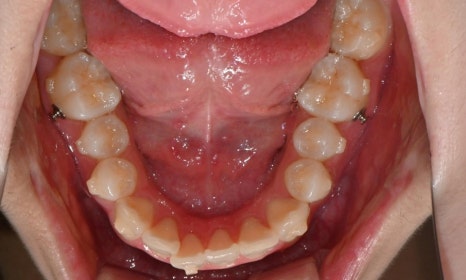

2025.3. 초진 (앞니 경미한 총생과 과개교합) - 연세정원치과

정밀진단 결과 위아래 앞니가 약간 겹쳐 있어 배열이 고르지 않은 상태였으며, 약간의 과개교합이 동반된 상태였습니다. 다만 골격적인 문제나 안모 불균형은 없었고, 측면에서도 돌출감 없이 비교적 안정적인 안모를 유지하고 있었습니다.

이러한 점을 종합적으로 고려해보았을 때 치아 배열의 개선과 교합 조정을 중심으로 한 비발치 교정 치료가 적합한 케이스였습니다. 또한 환자가 고등학생이라는 점, 그리고 학업과 일상 생활에 대한 부담을 최소화하고 싶다는 보호자의 의견을 반영하여, 인비절라인으로 선택하게 되었습니다.

이번 케이스는 인비절라인 Comprehensive로 치료를 진행하였으며, 치아 이동은 과도하지 않게 단계적으로 진행하기 위해 치간삭제를 최소한으로 적용하며 공간을 확보하는 방향으로, 총 33단계의 장치를 통해 치아 이동을 계획하였습니다.